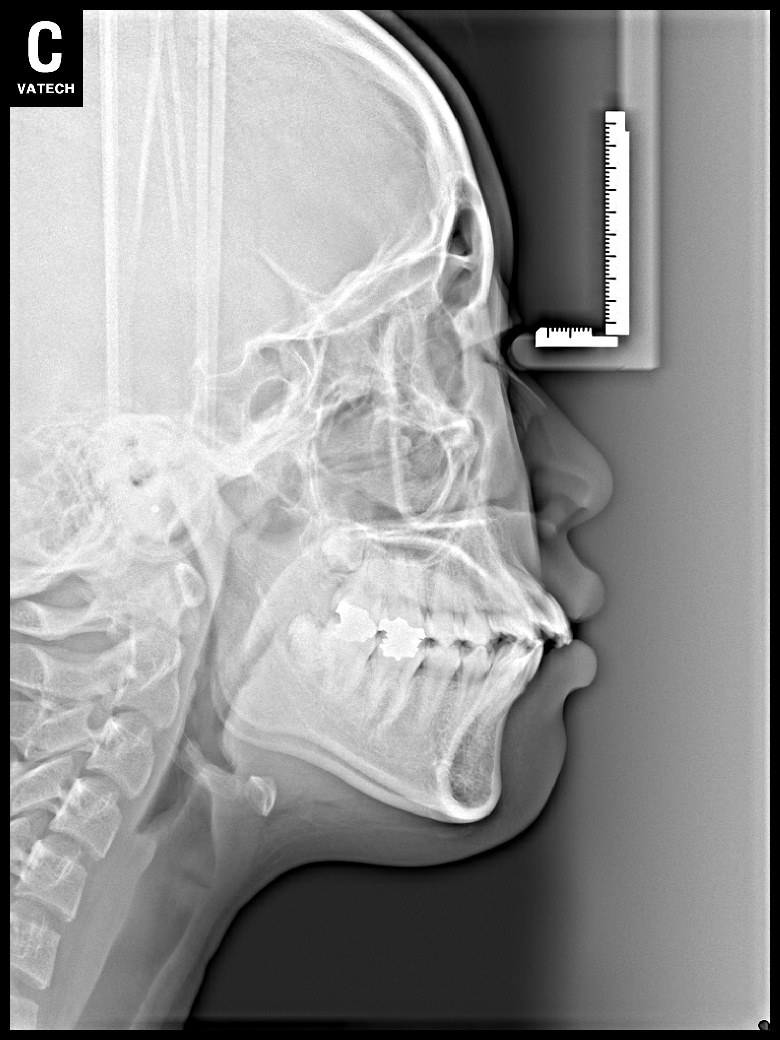

치료 전 사진입니다.